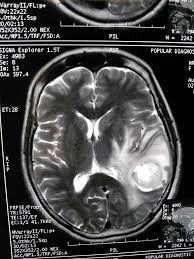

Vp shunt fracture. Ventriculoperitoneal vp shunts are a device used to shunt cerebrospinal fluid in the treatment of hydrocephalus. In follow up examinations we retrospectively reviewed patients who underwent revision surgery. Peritoneal catheter fractures occur most commonly in the neck the area where the tube is subject to mechanical stress.

The rate of shunt complications 1 month following insertion is 15 rising to 25 after 1 year and reaching 34 after 5 years 39 fig. Evidence based approach to complication prediction and avoidance during shunt surgery vp shunt surgery has a considerable long term complication rate. The shunt tubing is fractured at the level of the upper cervical spine.

Between 2006 and 2016 vp shunt surgery was performed on 1357 pediatric patients in our clinic. 5 6 the typical presentation of a fractured shunt system is usually quite late after initial insertion and it may be marked by the rapid onset of dramatic symptoms such as headache nausea swelling over the shunt tract often in a location over the shunt fracture or it may occur in a more subtle fashion over a longer period of time. As the name suggests a catheter is placed with its tip in the ventricle.

In follow up examinations we retrospectively reviewed patients who underwent revision surgery. The distal tubing is now coiled within the abdomen. Disconnection and fracture are two significant mechanical vp shunt dysfunctions and must be adequately researched and understood even during routine follow ups.

We have discussed the diagnosis and treatment approaches in patients with discontinued disconnected or fractured ventriculoperitoneal vp shunts that caused mechanical dysfunction. A disconnected or fractured shunt may be working and it is not safe to state that the shunt is no longer needed. Frontal radiograph of the cervical spine edge enhanced shows a fracture of the ventriculo peritoneal shunt drainage tube black and white arrows with caudal retraction of the distal fragment.

Between 2006 and 2016 vp shunt surgery was performed on 1357 pediatric patients in our clinic. 28097382 indexed for medline mesh terms. Ventriculoperitoneal vp shunt complications include blockage and infection early and prompt detection of shunt dysfunction is vital as delay can lead to markedly raised intracranial pressure coning and death.